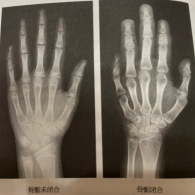

骨齡檢測

詳細說明骨齡檢測的流程、適用人群(生長發(fā)育異常兒童)、報告解讀方法(如G-P圖譜法、TW3法)及根據(jù)骨齡結果進行干預的時機與措施。